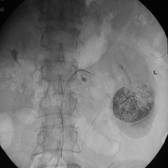

上图为同一病例双侧肾脏肿瘤造影表现,右侧肾脏行肾动脉主干栓塞后行右肾根治切除术,

左侧肾脏行超选择性肾动脉化疗栓塞术,术后可见碘油沉积肿瘤区。